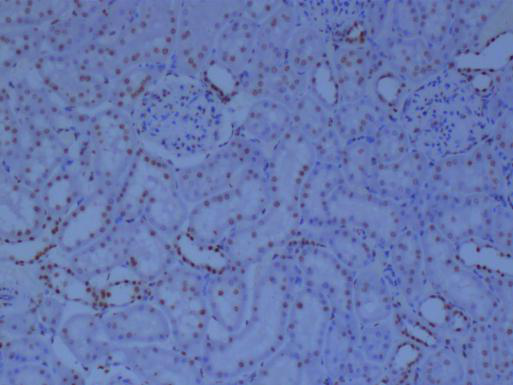

冰凍切片還可以用于免疫組化研究。通過冰凍切片技術(shù),研究人員可以制備含有特定抗原的組織切片,進(jìn)而利用免疫組化方法檢測(cè)和分析抗原的表達(dá)情況。這對(duì)于研究細(xì)胞的生物學(xué)功能、疾病的發(fā)生機(jī)制以及藥物的療效評(píng)價(jià)具有重要意義。